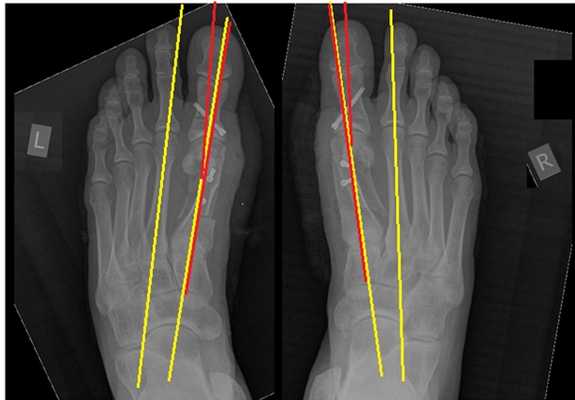

Клинический пример хирургического лечения hallux valgus 2 степени. Пациентка П. 32 лет, обратилась в клинику в связи с прогрессированием деформации 1 пальцев обеих стоп, усилением болей в области 1 плюсне-фаланговых суставов обеих стоп, трудностями с подбором обуви. Вальгусная деформация 1 пальцев или Hallux Valgus является наиболее частой причиной обращения за хирургической помощью к ортопедам, занимающимся проблемами стоп.

При клиническом осмотре обращает на себя внимание наружное отклонение 1 пальцев, расширенный и уплощённый поперечный свод стопы, нарушение плюсневой формулы, гиперкератозы по внутренней и тыльной поверхностям 1 плюсне-фаланговых суставов.

При планировании оперативного пособия выполняются рентгенограммы в прямой и боковой проекции. Производится расчёт углов вальгусного отклонения 1 пальца, угол между 1 и 2 плюсневыми костями, угол артикуляции 1 плюсневой кости. Исходя из рассчитанных углов, выбирается оптимальный метод остеотомии для коррекции имеющейся деформации.

Хирургическая тактика обсуждается с пациентом. Разъясняются особенности хирургического доступа, анестезиологического пособия, последующей реабилитации. Эту пациентку беспокоила деформация только 1 луча, вмешательства на 2-3-4-5 лучах стопы не потребовались.